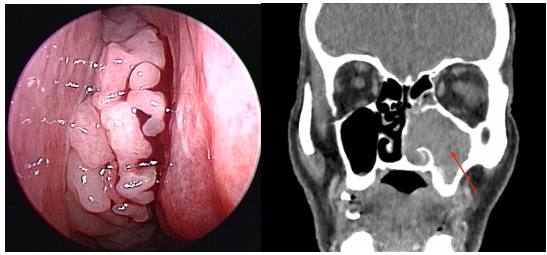

Aspecto endoscópico e tomográfico da lesão

O diagnóstico é feito através do exame físico, endoscopia nasal com a visualização direta da lesão e exames de imagem como a tomografia e a ressonância dos seios da face sendo confirmado apenas com biópsia.